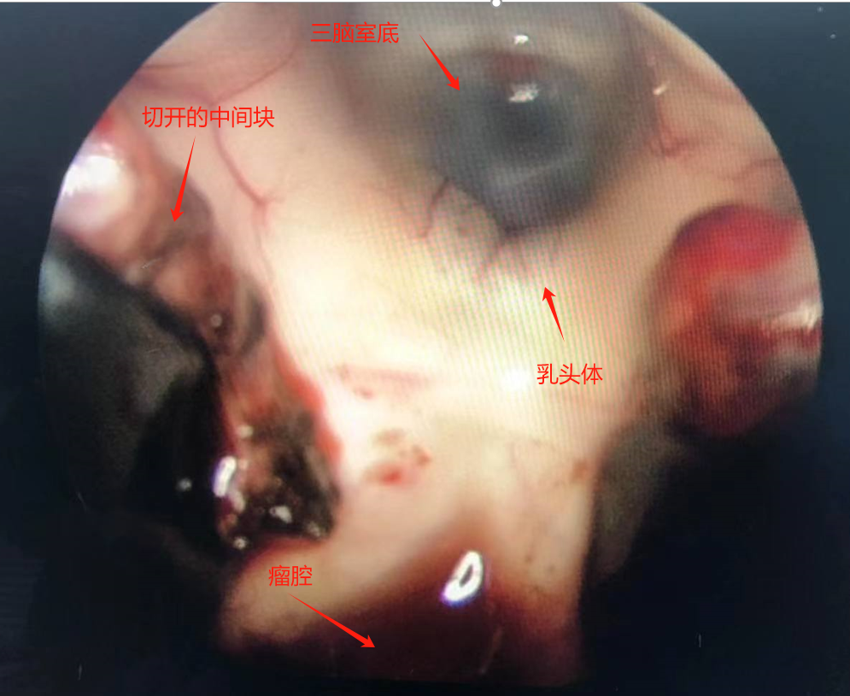

诊治过程:结合患者临床表现及影像学表现,初步诊断考虑为三脑室后部胶质瘤合并梗阻性脑积水可能性大,术前制定的手术方案为经胼胝体穹隆间入路三脑室后部肿瘤切除术+脑室镜辅助下三脑室底造瘘术,该手术方式既可切除肿瘤获取病理,同时可行三脑室底造瘘解决脑积水症状。术中采用冠状缝前额部弧形切口,术中沿纵裂牵开双侧大脑半球,探及胼胝体,沿中线切开胼胝体,分离双侧透明隔,暴露双侧穹隆,严格沿中线分离双侧穹隆,保护两侧穹隆的完整,避免引起术后的记忆力障碍,牵拉开双侧穹隆,进入中间帆,显露并分离双侧大脑内静脉继续向下,经脉络膜隔进入三脑室,完全显露肿瘤组织,肿瘤组织呈灰红色,血供极其丰富,与中脑黏连紧密,仔细分离,分块全切肿瘤,双侧大脑内静脉及中脑保护良好,中脑导水管通畅。肿瘤完全切除后,考虑到术后局部粘连、肿瘤复发等因素可能导致脑积水不缓解,置入脑室镜向前方探查,小心切开中间块,在双侧乳头体与漏斗隐窝之间,行三脑室底部造瘘并打开Liliequist膜及基底动脉旁蛛网膜,确认漏口通畅且与脚间池相通。患者术后恢复过程平稳,颅脑MRI提示肿瘤切除满意,脑积水缓解。术后病理结果示:中枢神经细胞瘤(2级)。术后予以放疗GTV 5400cGy、PTV 5040cGy,28f。现术后已3年,复查未见肿瘤复发,脑积水已完全缓解。